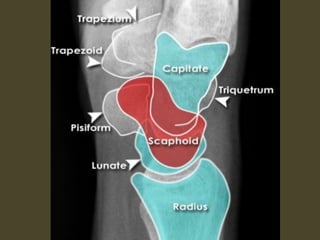

Wrist X-ray Anatomy.

A simple approach is to consider the lunate

which is usually the easiest carpal bone to

visualize on a lateral wrist image. If the

lunate is abnormally tilted in a dorsal

direction on a standard lateral wrist image,

a DISI should be considered. If the lunate is

abnormally tilted in a volar direction a VISI

should be considered. DISI is due to

disruption of the scapho-lunate articulation.

VISI is secondary to disruption of the luno-

triquetral articulation.